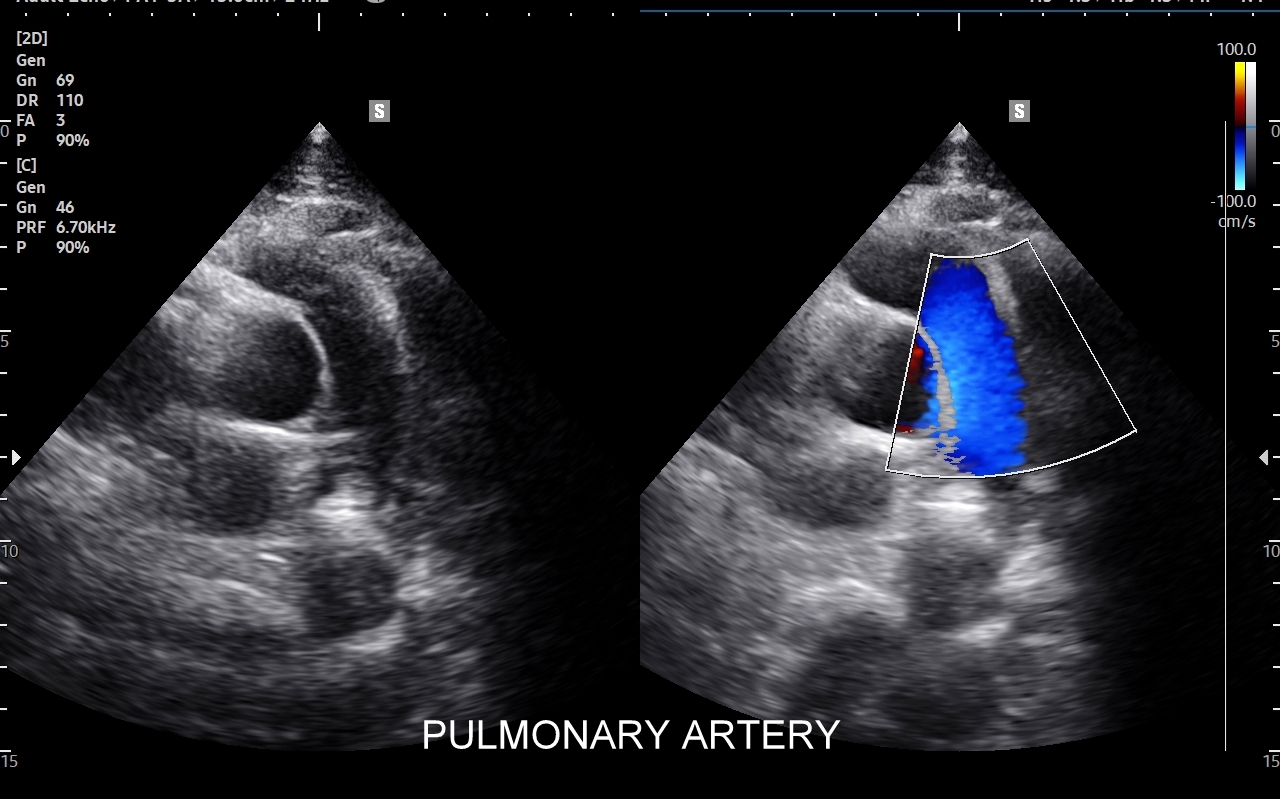

Czym są tętnice? Tętnice to naczynia krwionośne, którymi krew wypływa z serca i dociera do tkanek i narządów w organizmie. W tzw. krążeniu dużym tętnice transportują krew utlenowaną, a w krążeniu małym krew odtlenowaną w kierunku płuc. Zdrowe tętnice są okrągłymi w przekroju naczyniami o elastycznych ściankach, cienkim i gładkim śródbłonku; panuje w nich wyższe ciśnienie w porównaniu do naczyń żylnych. W związku z pełnioną zasadniczą funkcją, tj. transportem tlenu oraz substancji odżywczych do praktycznie wszystkich tkanek w ciele człowieka zdrowe tętnice są narządami warunkującymi długowieczność. Jak sprawdzić stan zdrowotny tętnic? W badaniu USG.

Choroby tętnic. Najczęstszą chorobą tętnic jest miażdżyca, która naturalnie i powoli rozwija się wraz z wiekiem, jednakże może ulec znacznemu przyspieszeniu i nasileniu pod wpływem takich czynników jak palenie papierosów, cukrzyca, zaburzenia lipidowe, czy nadciśnienie tętnicze. Rozwijająca się miażdżyca doprowadza do zwężeń naczyń tętniczych, a czasem nawet do ich zamknięcia wywołując objawy niedokrwienne. Przykładami ostrych chorób niedokrwiennych jest udar mózgowy oraz zawał serca. Z kolei przykładami przewlekłych zespołów związanych z miażdżycą są demencja, angina brzuszna i chromanie przestankowe. Inne choroby tętnic obejmują m. in. tętniaki, rozwarstwienia, zapalenia, czy zespoły podkradania, których cech poszukuje się w trakcie wykonywania badania USG Doppler tętnic.